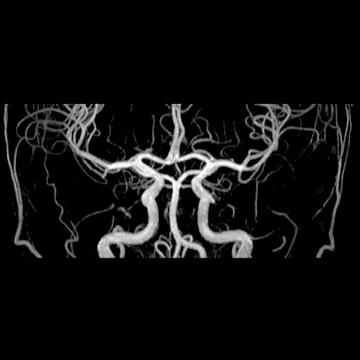

頭部MRA

matrix 320, FOV 220 mm- 頭部MRA